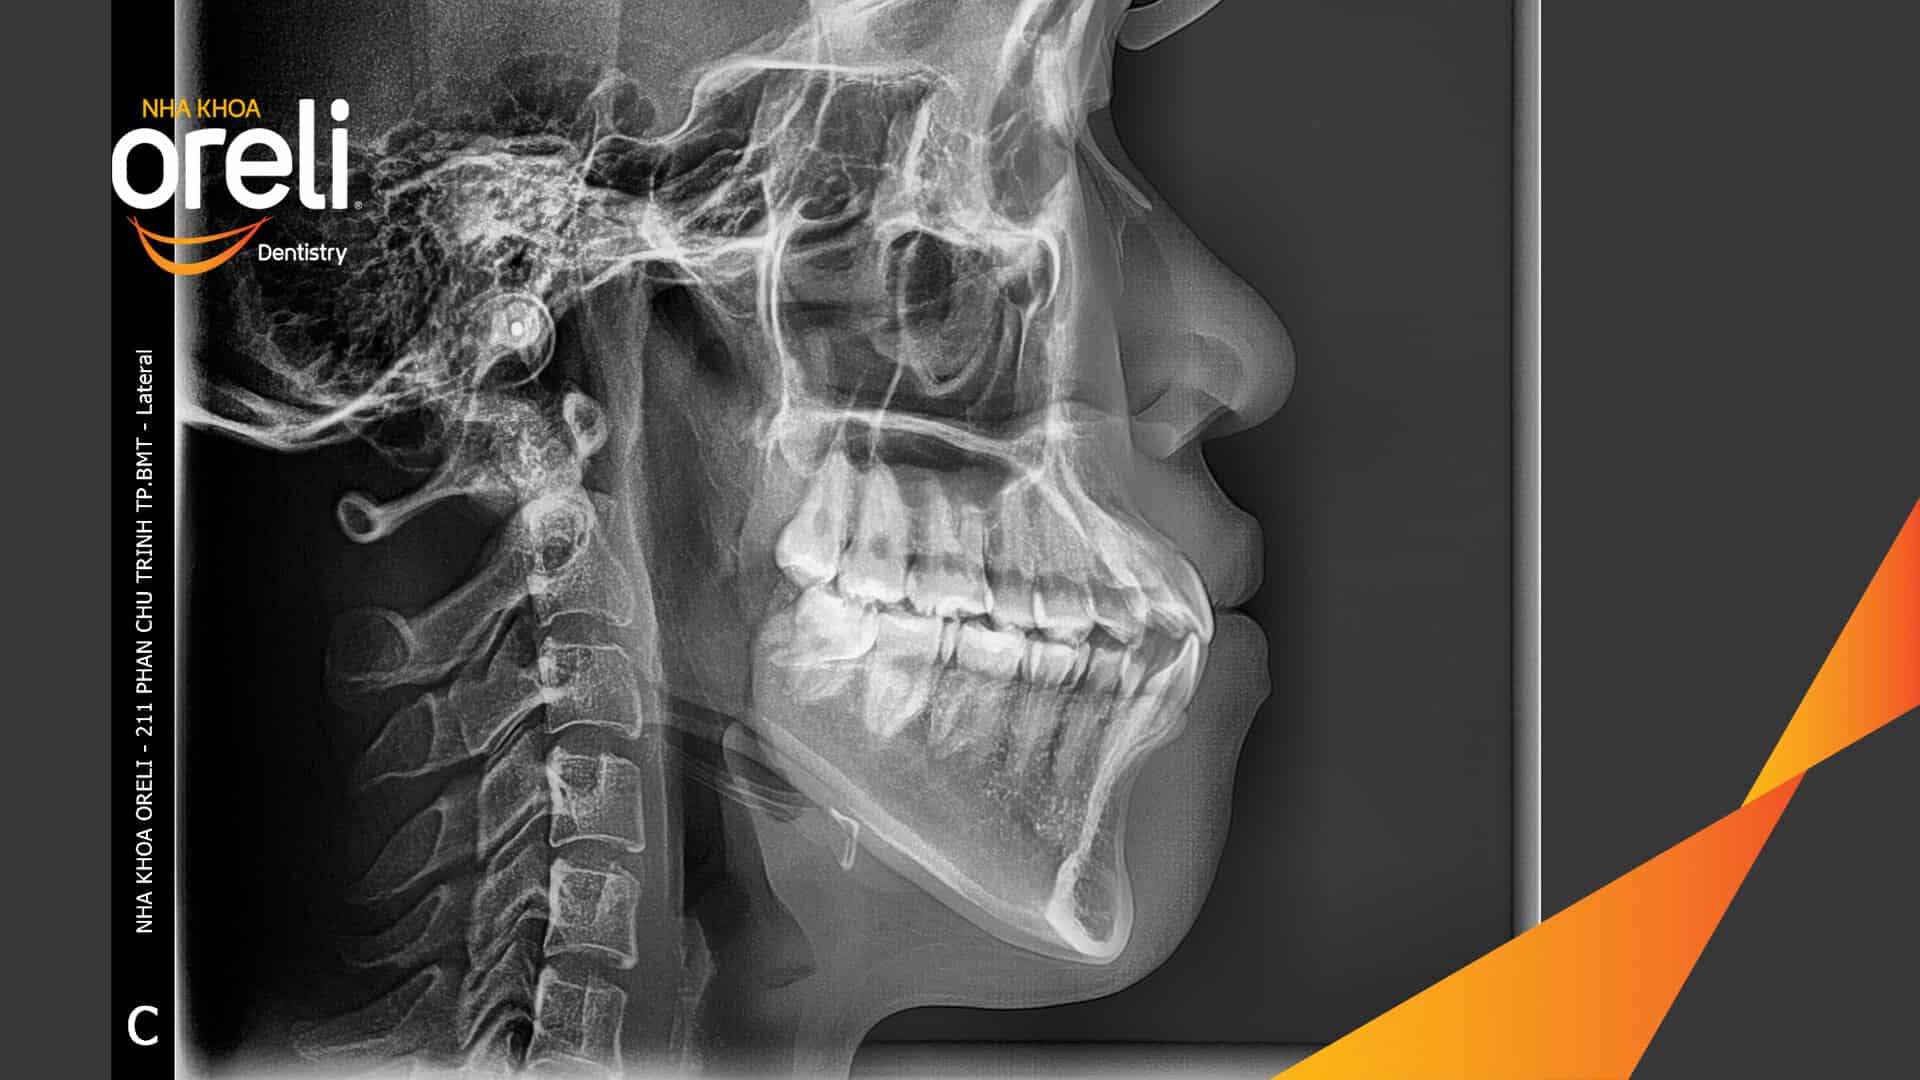

Ca niềng răng sai khớp cắn hạng 3 móm nặng có nhổ răng số 7 – Kết quả thực tế Niềng răngChỉnh lệch cằmMóm Xem thêm